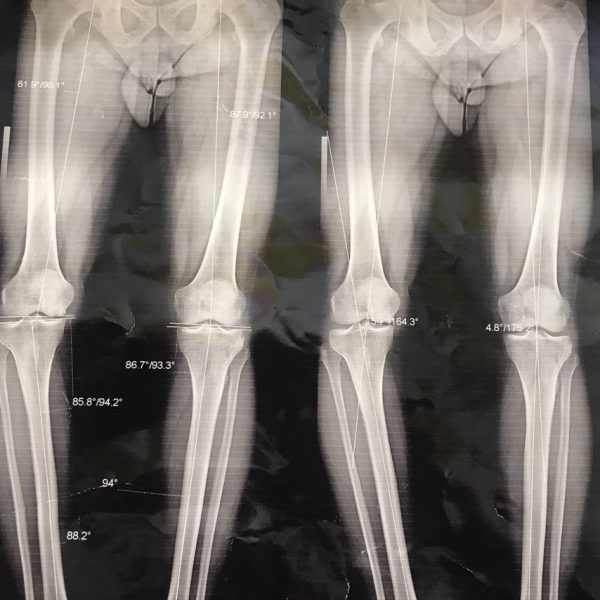

Fractures inside the knee joint

The patient came to us with the problem of fractures inside the knee joint around the knee joint. PatientIranianProblemKneereferenceFarvadin 1400diagnosisFractures ... Read More